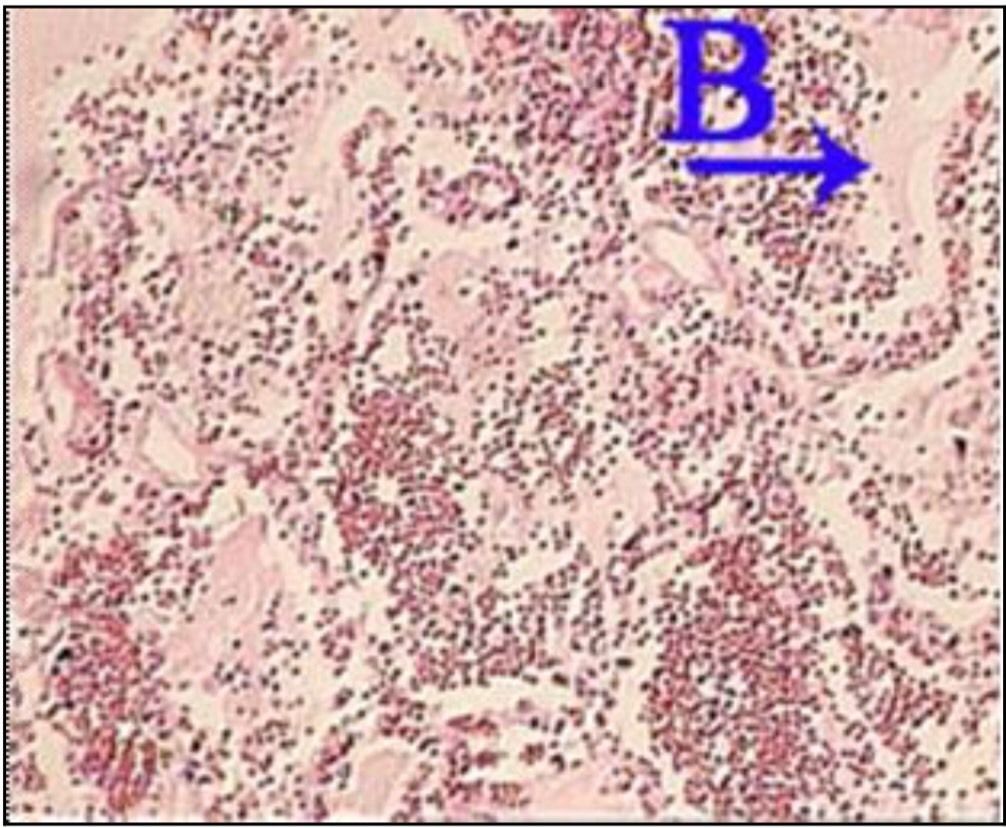

Question 107

Question

What is the correct answer at point A?

Answer

• - formation vasculaire de l’hémangiome

• - septa conjonctif

• - endothélium capillaire

• - globules rouges

• - lumière contenant de globules rouges

Question 108

What is the correct answer at point B?